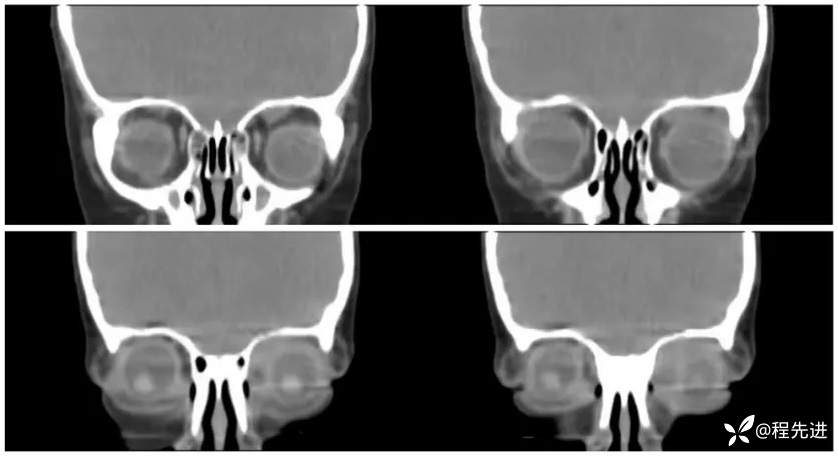

CT平扫: